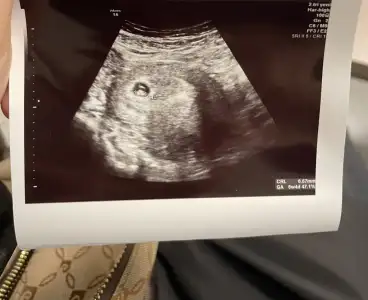

Benim bebitoOrtadaysa ne olur

Canım banada bakar mısınBenim bebito

ortafa görünüyor ama dikkatli bakınca solda plesenta görünüyor

Plasenta nerde anlamıyorum benCanım banada bakar mısın